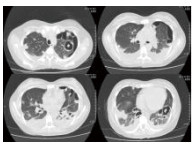

入院相关化验结果,血常规:WBC 0.8 g/L, NE 0.5 g/L, HGB 126.0 g/L, PLT 47.0/L;血气分析:pH 7.450,PaCO2 32.90 mmHg,PaO2 52.50 mmHg,SaO2 89.3%, LAC 3.9 mmol/L, HCO3- 22.5 mmol/L;心肌标志物:CK 4 668 U/L,MB 46.2 ng/mL,cTnI 0.52 ng/mL,MyO 1 884 ng/mL;肾功能:UREA 7.10 mmol/L,CREA 80.7 μmol/L,Glu 8.35 mmol/L,Na+ 131 mmol/L,K+ 3.9 mmol/L;肝功能:ALT 47 U/L,AST 211 U/L,ALB 22.4 g/L,TBIL32.93 μmol/L,DBIL 19.01 μmol/L; D-Dimer 18 893 μg/mL;BNP 986 pg/mL;ESR 66 mm/h;CRP 320 mg/L; 降钙素原53.8 ng/mL。腹部B超(-);子宫附件B超(-);超声心动图(-)、入院前胸部CT平扫提示双肺多发片状、团块病灶,见图 1。

| 图 1 入院前胸部CT |

2.4 影像学除外肺部转移瘤的原因分析患者住院时高热,喘憋比较明显,影像学提示双肺弥漫性浸润病灶(图 1)。最初考虑可能为多发肺部转移瘤?随着治疗的好转以及影像学的演变,最终排除了肺部转移瘤的诊断。